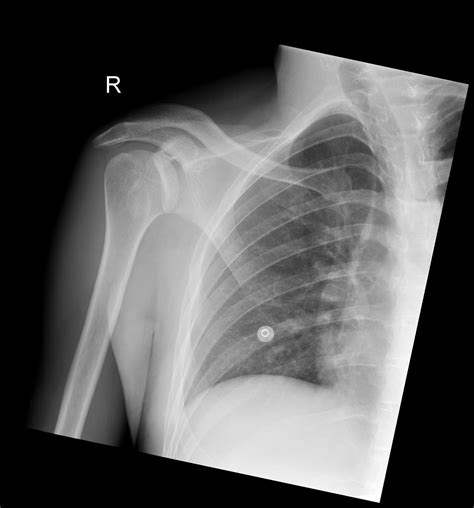

• Imaging Tests: X-rays are the primary imaging tool used to confirm the diagnosis. Additional tests such as CT scans or MRIs may be ordered to evaluate the extent of the injury and any associated damage to surrounding tissues.

Diagnosis of Posterior Shoulder Dislocation

Diagnosing posterior shoulder dislocation involves a combination of physical examination and imaging tests. The diagnostic process typically includes: